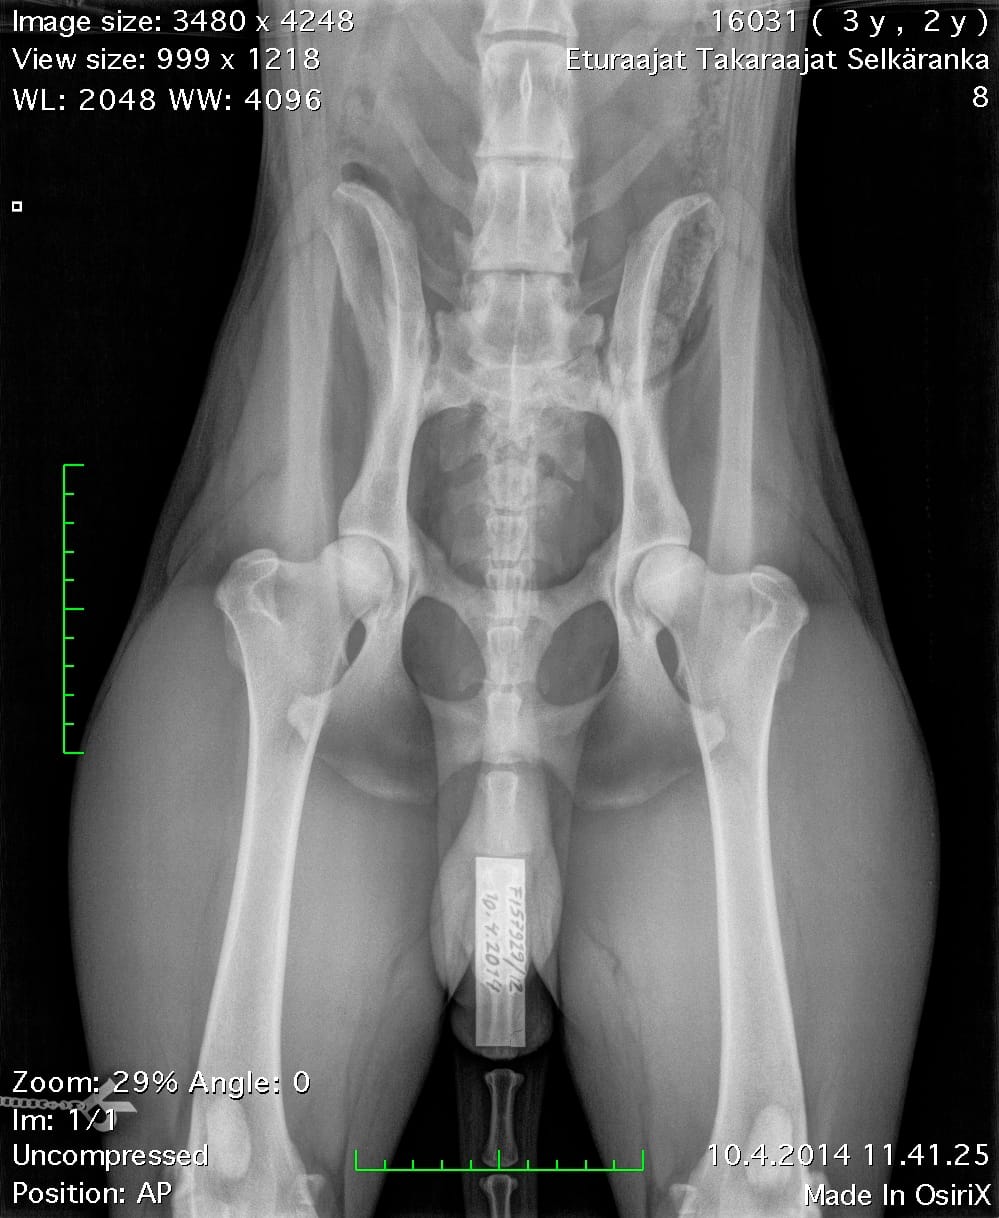

| Hips: | A/A | |

| Elbows: | 0/0 | |

| Spine: | SP0, LTV4 (8 lumbosacral vertebrae) | |